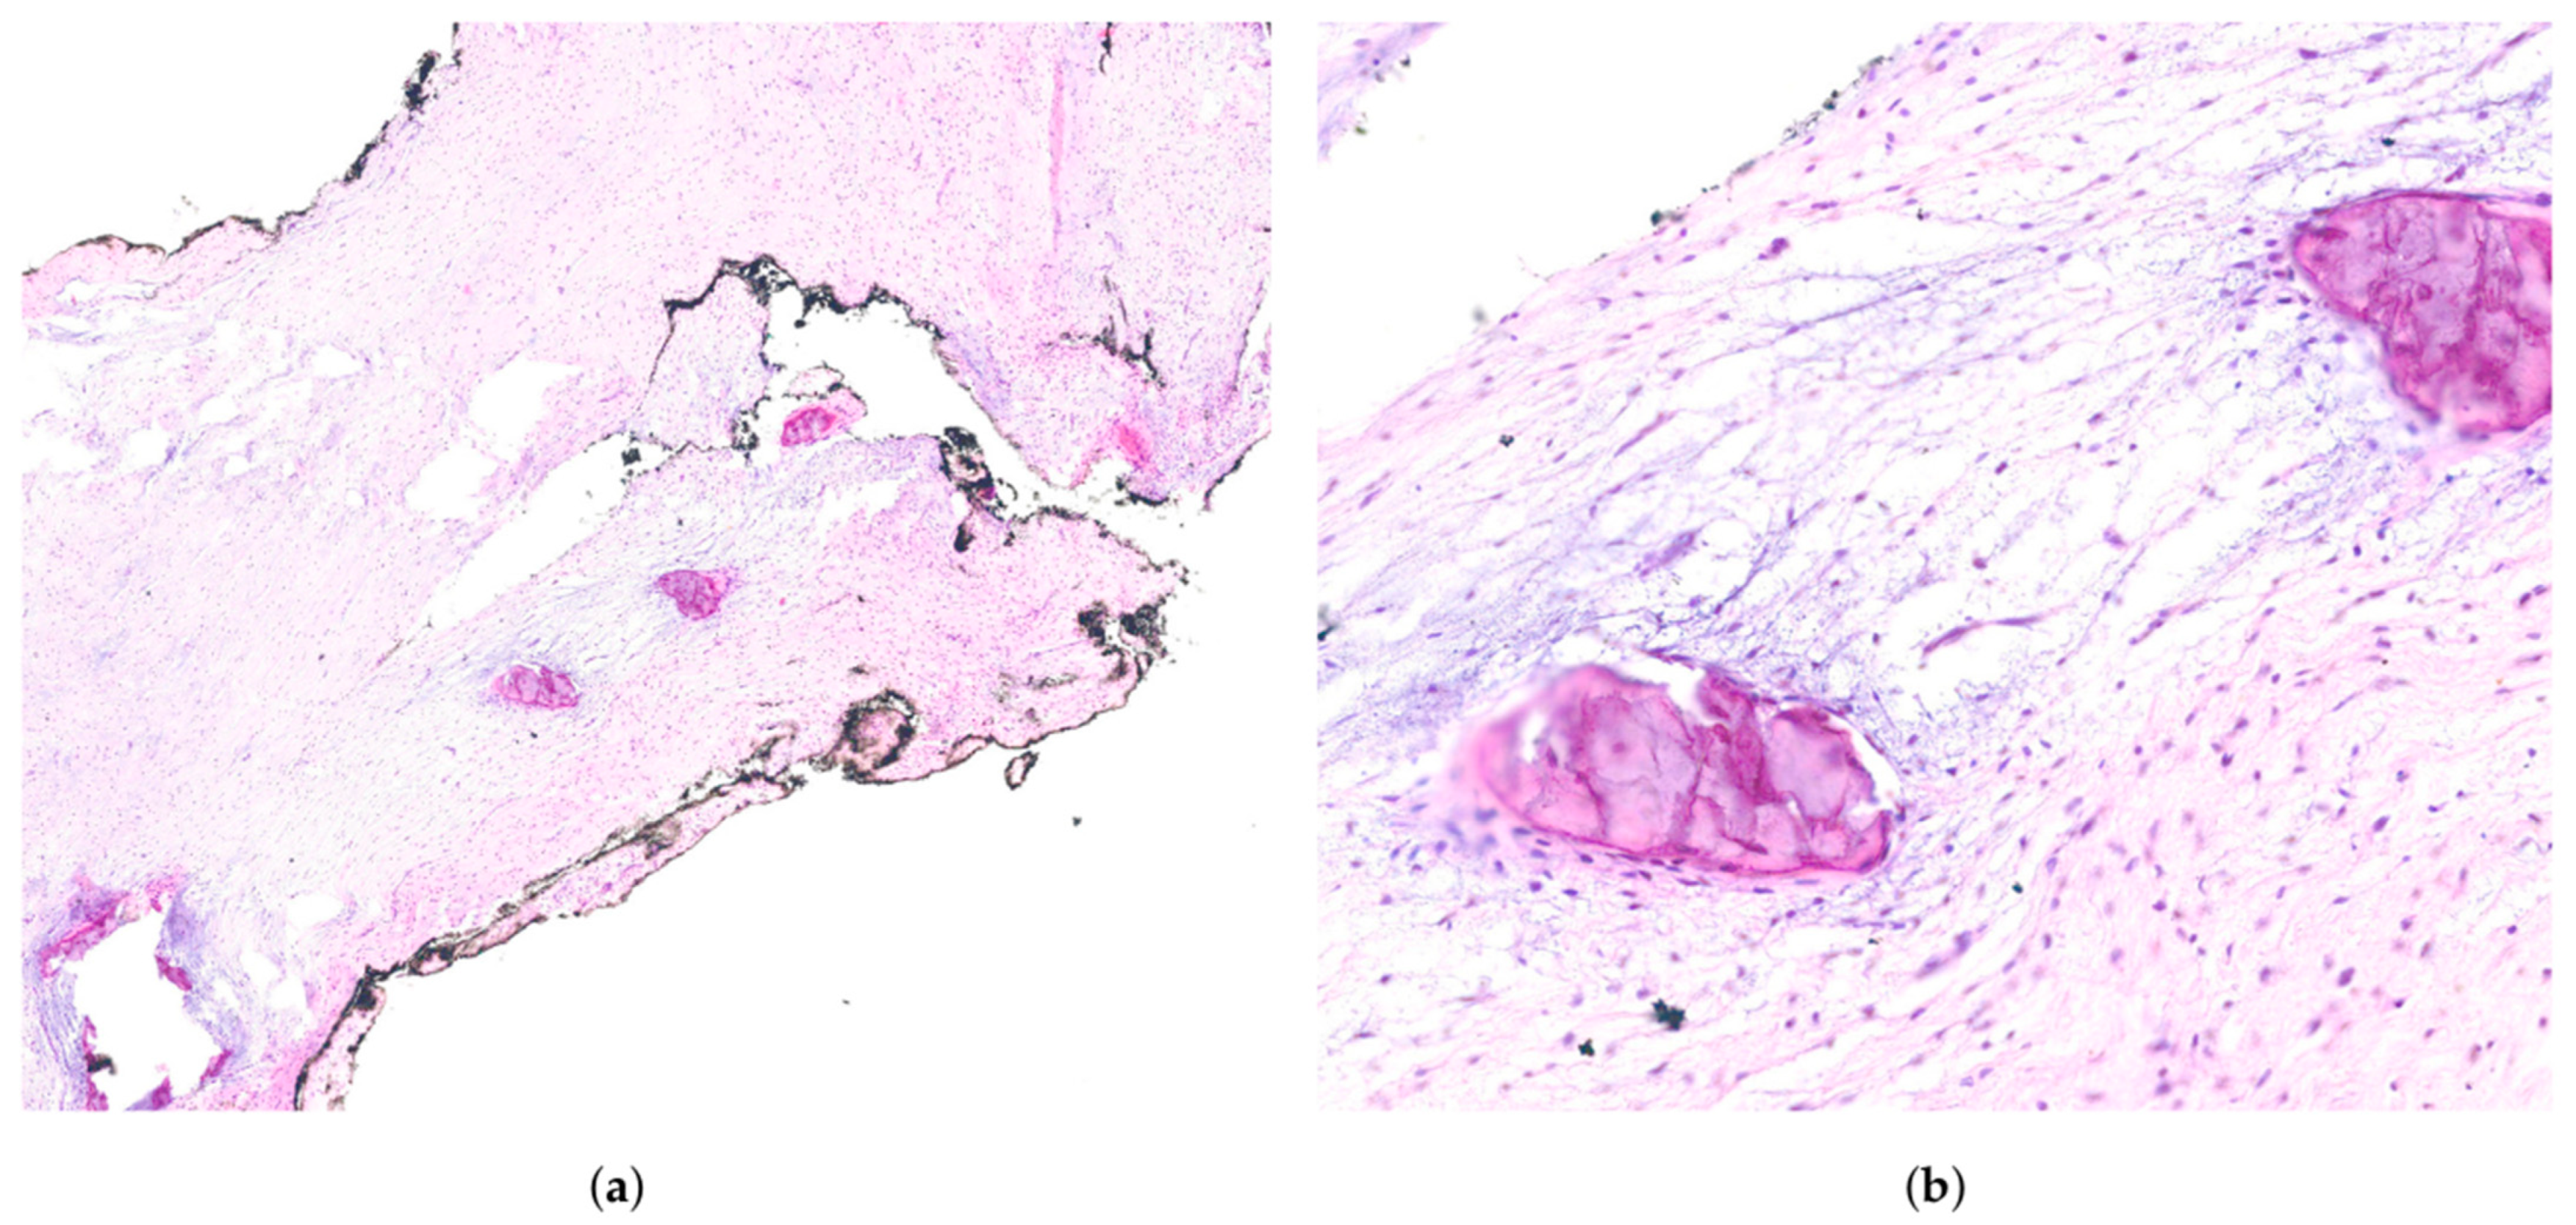

2.2. Treatment Procedures and Histopathological Results

| Histology and Odontogenic Epithelium | Spindle and stellate-shaped cells in a myxoid stroma with prominent collagen fibres. Possible remnants of odontogenic epithelium, aiding differentiation from odontogenic myxoma | [4,13,14] |